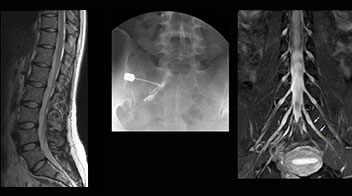

“In such case, we would then browse through axial T2-weighted MR images slice by slice and mentally reconstruct the actual situation based on both radiculography and MRI. Fortunately, NerveVIEW can now very well show nerve courses and presence of nerve compression or edema in one single image series.” “We have often seen NerveVIEW directly depict details of the nerve compression that were not observed by radiculography. Therefore, we think that with NerveVIEW we can reduce the number of invasive examinations, especially for some patients with lumbar plexus symptoms.”

“Before NerveVIEW, diagnosis by MRI alone was sometimes difficult, unless there was a strong suspicion based on clinical symptoms,” says Shoji Yabuki, MD, DMSc, Orthopedic surgeon at Fukushima Medical University School of Medicine. “This is why we routinely perform selective lumbosacral radiculography (nerve root block) and x-ray in such cases. However, radiculography can only depict nerves as far as the contrast agent reaches. When a nerve is distorted by compression, the contrast agent will not pass through this compressed area, preventing us from evaluating the full nerve compression.”

The key concept in MR neurography, Dr. Yabuki stresses, is the ability to directly visualize spinal nerves, versus inferring the presence of pathology indirectly. “Before NerveVIEW, we estimated compression of the nerve by looking for the presence or absence of fat signal on other MR images,” he says.

“For example, in sagittal images, when the presence of fat is observed in the intervertebral foramen, it suggests that there is a margin around the nerve. Similarly, the absence of fat indicates that the nerve is being compressed. So, we used to deduce nerve compression indirectly. With NerveVIEW, however, we can observe the condition of the nerves directly, regardless of the presence or absence of fat. We always prefer such direct observation of anatomy over having to make an inference about it.”

“Although symptoms of typical disc herniation and atypical hernia are very similar, the actual site of herniation is different. It is therefore important to characterize the nerve’s condition both inside and outside of the intervertebral foramina. “Conversely, if we see no abnormality in NerveVIEW, we can assume at least that there is no severe condition that requires surgery. Like this, it can help us avoid unnecessary surgery. NerveVIEW can have a tremendous impact in this way.”

“NerveVIEW is really useful for those cases where a nerve disorder is strongly suspected based on the clinical examination but our regular MRI images do not show any findings. These atypical herniations and spinal canal stenosis, occurring in 5% to 15% of the total lumbar herniation/stenosis cases are our main target when using NerveVIEW,” says Dr. Yabuki.

“The intra-luminal signal of veins, especially around the intervertebral space, can be suppressed well with NerveVIEW. As a result, we can easily observe the detailed nerve structure around the posterior ganglion,” he says. “This is why we use 3D NerveVIEW for intraforaminal stenosis and extraforaminal stenosis/herniation (lateral disc herniation). On the other hand, if herniation is suspected to exist inside the dorsal root ganglion (DRG), balanced TFE or ProSet-FFE is applied. NerveVIEW is not suitable for evaluating the median type of herniation.” The SE-EPI DWI-based method for MR neurography works well for large FOV exams like whole-body MRI, but focal examination of nerves is often limited by the attainable spatial resolution (both inplane and slice direction) and geometric distortion. “3D NerveVIEW achieves higher in-plane resolution – close to our other routine spine sequences – and the source images can be used instead of adding a fat-suppressed T2-weighted sequence,” Tanji says.